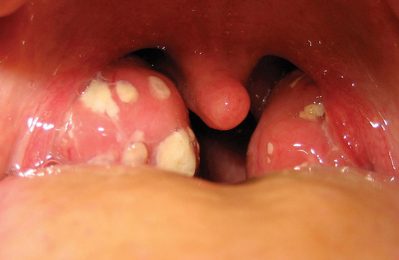

Viêm amidan có mủ ở người lớn là một căn bệnh thường gặp với các triệu chứng đau họng, sốt và xuất hiện mủ trắng...